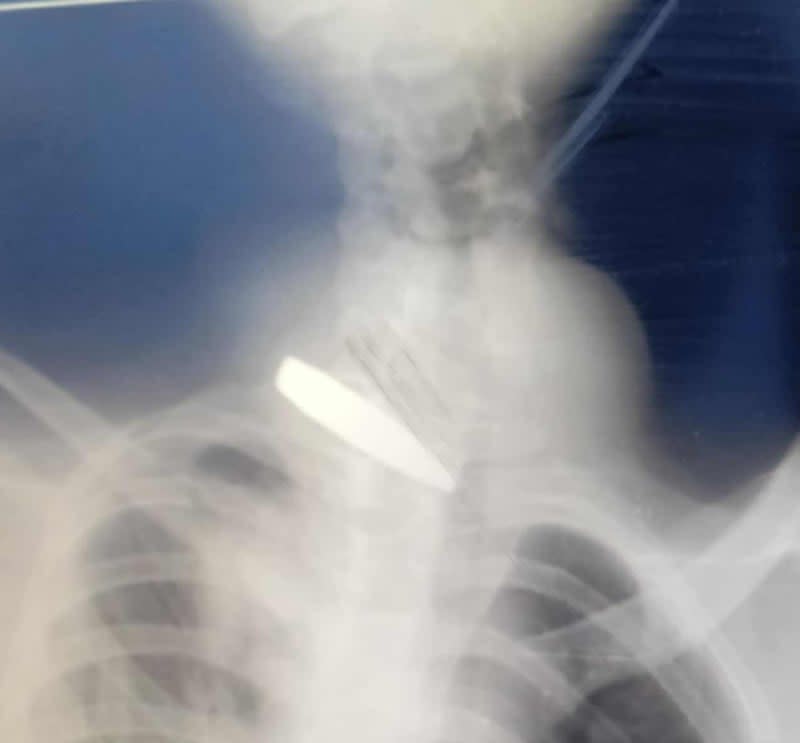

Liknande text är mejlad till sjukvårdsminister Elisabet Lann. Bilden är en preoperativ röntgen från en av de drabbade i artikeln. Flera tidningar har nekat publicering av denna text.

I Rapport den 6 februari i år sa du att det finns en chans att Sverige skulle kunna ta emot patienter från Gaza om de inte kan få vård i Egypten. Då väcktes hoppet hos oss. Under februari i år har hittills 211 patienter evakuerats från Gaza till Egypten. (https://www.unocha.org/publications/report/occupied-palestinian-territory/gaza-humanitarian-response-situation-report-no-68) En av dem är Muhammed. I december 2024, när han var 16 år gammal besköts han från en stridsvagn när han låg och sov i ett tält i en zon som Israel hade förklarat som säker. Kulan slet med sig hans ryggrad och punkterade en lunga. Sjukvården i Gaza lyckades rädda hans liv, men han blev förlamad. Eftersom sjukvården i Gaza har förstörts har anhöriga hela tiden försökt få Muhammed evakuerad för att kunna få mer kvalificerad vård.